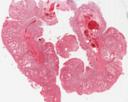

41-28: Juveniler Polyp (HE)